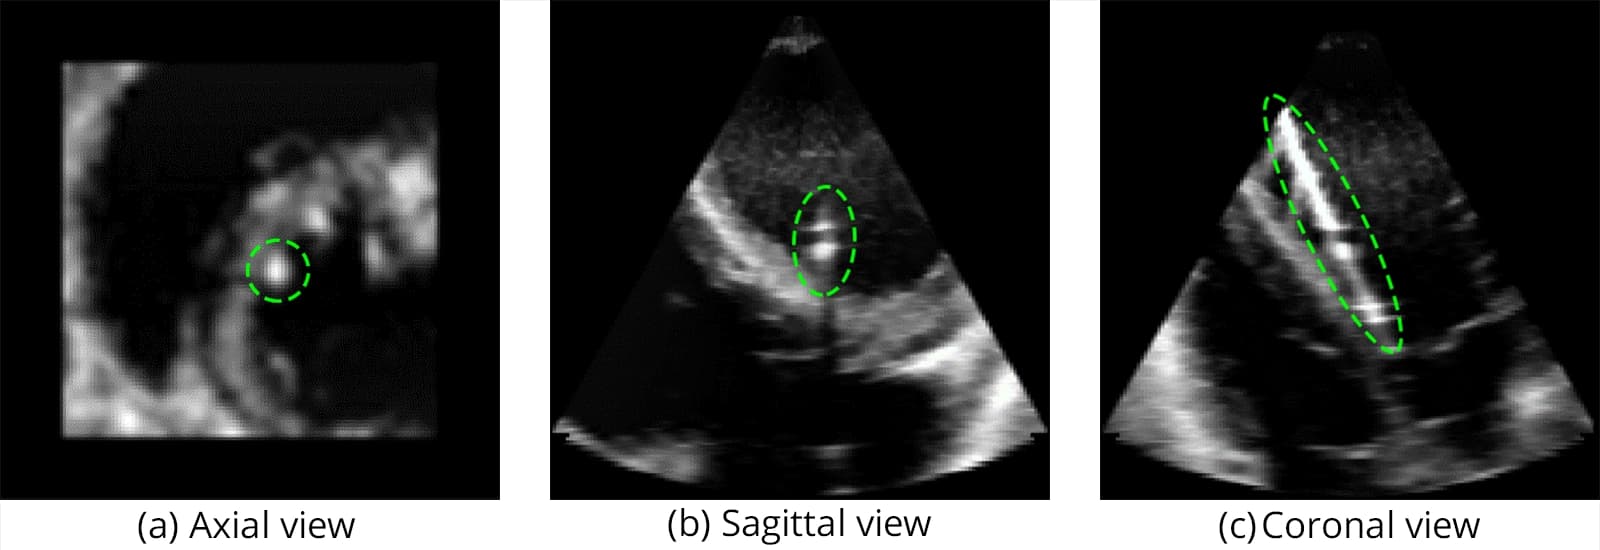

The catheter used in this study is shown in Figure 1, while Figure 2 illustrates the challenging visibility of catheters in raw ultrasound data.

Segmentation accuracy on synthetic and real samples is shown in Figure 5 and Figure 6, and the comparison with other networks is presented in Figure 7.